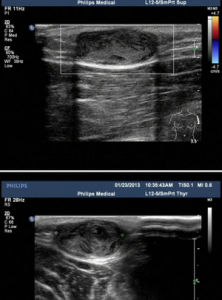

在顱骨縫間皮樣囊腫,必要時查“B”。